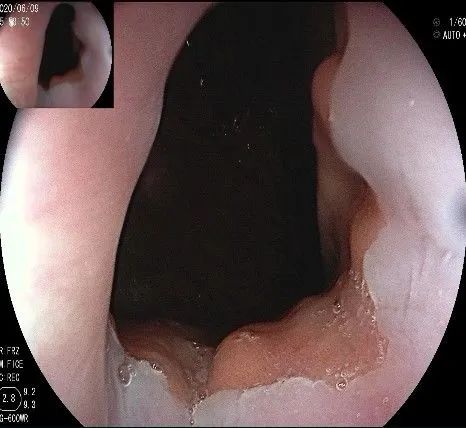

倒镜观察,可见贲门部一个明显的隆起,中央部分的凹陷,是4天前取活检留下的。

我们的思路:病变长径约2.0cm,位置活动,倒镜后先在胃底侧粘膜下注射,使病变向食管腔方向抬举,然后再在食管腔内做粘膜下注射切开,以获得一个好的术野,果然,注射后粘膜抬举明显,瘤体被挤向口侧。

正镜观察,瘤体就在贲门部齿状线的下方。